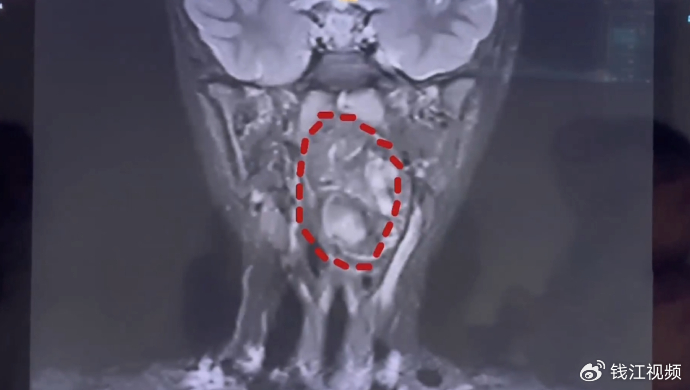

慌乱中,母子俩前往复旦大学附属儿科医院就诊。经该院耳鼻咽喉头颈外科副主任陈超诊断,这枚肿瘤是由生殖细胞长成的畸胎瘤,“我们可以看出它有脂肪,有软骨,这是一对双胞胎,一个是正常发育成的人,另外一个可能残留在这个咽旁间隙里面,就发育成了这样的一个畸胎瘤。”

检查显示,小亮的口咽腔仅8厘米左右,而6.6×3.5×3厘米的肿瘤已占据大部分气道,仅留一条缝隙透气,若不及时手术,可能导致呼吸道梗阻窒息。更棘手的是,肿瘤紧贴颈内颈动脉,手术出血风险极高。